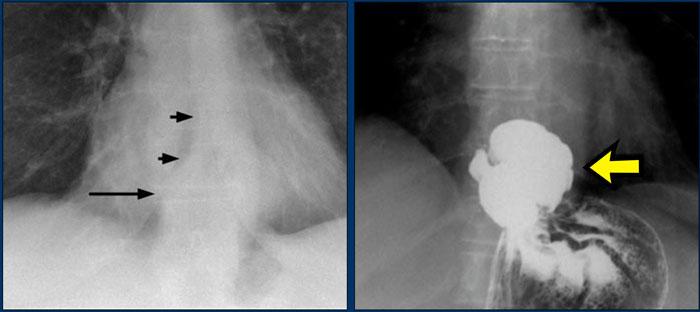

Trên phim X-quang ngực tư thế PA, có thể thấy đường tĩnh mạch đơn–thực quản bị lệch sang bên.

Nguyên nhân là do thoát vị khe thực quản.

Mũi tên chỉ vào thuốc cản quang barium trong túi thoát vị khe thực quản.

Dấu hiệu hình ảnh

- Dịch chuyển đường azygô-thực quản cả lên trên lẫn xuống dưới

- Hình ảnh mức khí-dịch, phù hợp với thực quản giãn chứa dịch

- Đám mờ quanh rốn phổi trái ở vùng lưỡi phổi, được cho là do viêm phổi hít trước đó